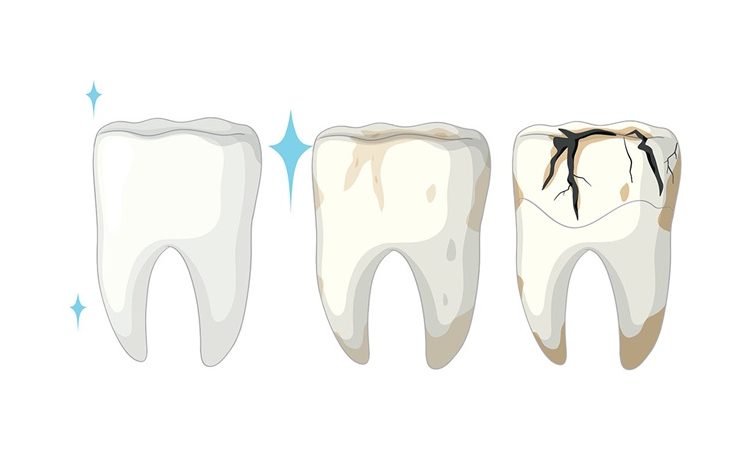

چگونه دندان آسیبدیده را حفظ کنیم؟ ترمیم مستقیم دندان ترکخورده یکی از روشهای مهم در دندانپزشکی است که به حفظ ساختار دندان و جلوگیری از کشیدن آن کمک میکند. ترک دندان میتواند ناشی از پوسیدگی، فشار جویدن یا ضربه باشد و درمان به موقع اهمیت زیادی دارد. در این مقاله از سایت دکتر حسین برجیان

راهکاری سریع و موثر دندانهای ترکخورده ناشی از پوسیدگی یکی از مشکلات شایع در دندانپزشکی هستند که در صورت عدم درمان میتوانند به شکست کامل دندان منجر شوند. ترمیم مستقیم دندان با مواد همرنگ دندان، راهکاری سریع و مؤثر برای بازگرداندن عملکرد و زیبایی است. در این مقاله از سایت دکتر حسین برجیان (بهترین دندانپزشک